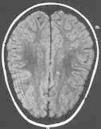

Paciente varón de 11 años de edad sin antecedentes personales de interés remitido desde atención primaria por un cuadro clínico agudo de cefalea y visión borrosa. En el momento de la consulta el paciente se encontraba asintomático. Refería cefalea habitual que en el último mes había aumentado de intensidad y periodicidad, de características pulsátil, localización bitemporal, predominio matutino, que aumentaba con los movimientos de la cabeza y que cedían con analgesia habitual. Se acompañaba de anorexia, pérdida ponderal, labilidad emocional y visión borrosa de manera intermitente. Como antecedentes familiares de interés destacaban numerosos diagnósticos de migraña en la rama materna. La exploración física y neurológica detallada fueron normales. Se le realizó examen de fondo de ojo donde destacaba una discreta palidez de ambas papilas del nervio óptico. Se le practicó una TC, que fue normal, y una punción lumbar que objetivó una presión de apertura de 360 mmH2O, con citoquímica y bioquímica normal. El cultivo y el estudio viral en LCR resultaron estériles. En la RM cerebral se apreciaron pequeñas alteraciones puntiformes de aumento de señal en sustancia blanca subcortical de ambos lóbulos frontales y temporal derecha en densidad protónica y en secuencia T2 (fig. 1). La resonancia por angiografía fue normal. La agudeza visual estaba disminuida (ojo derecho, 0,7, y ojo izquierdo, 0,8) y en la campimetría se apreciaba una pérdida visual bilateral (ojo izquierdo 14/120; ojo derecho 22/120). Los potenciales visuales evocados manifestaban retraso de latencia en la vía óptica, sobre todo izquierda. El estudio de autoinmunidad fue normal. El estudio de hipercoagulabilidad reflejó un estado de heterocigosis para el factor V de Leiden con una resistencia para la proteína C (ratio): 1,87 (normal: 2-5). El estudio familiar desveló el estado de heterocigosis del padre con una resistencia a la proteína C (ratio): 1,65 (normal: 2-5).

Figura 1.Caso 1. Lesiones hiperintensas puntiformes sugerentes de microinfartos.

En el fondo de ojo se apreció una lesión tipo pars planitis bilateral. La TC fue normal. La punción lumbar objetivó una PIC de 420 mmH2O. La citología, bioquímica y cultivos fueron normales. La RM craneal destacaba hiperseñales en secuencias T2 inespecíficas en la sustancia blanca frontal adyacente al asta frontal del ventrículo lateral izquierdo (fig. 1). La resonancia craneal por angiografía fue normal. La agudeza visual de 0,8 en ojo derecho y 0,7 en ojo izquierdo. El estudio de autoinmunidad fue normal. En el estudio de hipercoagulabilidad presenta mutación del gen del FVL en estado de heterocigosis, con una resistencia a la proteína C activada (ratio) de 1,67. El resto del estudio de coagulación y homocisteína fue normal.

Se sugiere que los microtrombos de la vellosidades aracnoideas dificultaría la reabsorción del LCR. La trombosis de los pequeños vasos cerebrales, la agresión isquémica y el daño microvascular aparecen como la explicación fisiopatológica a la asociación de HIB y los estados de hipercoagulabilidad 7. En nuestros pacientes no hemos encontrado evidencia de lesión del árbol cerebrovascular; sin embargo, las lesiones difusas inespecíficas en secuencias T2 en la sustancia blanca podrían sugerir microinfartos vasculares cerebrales.